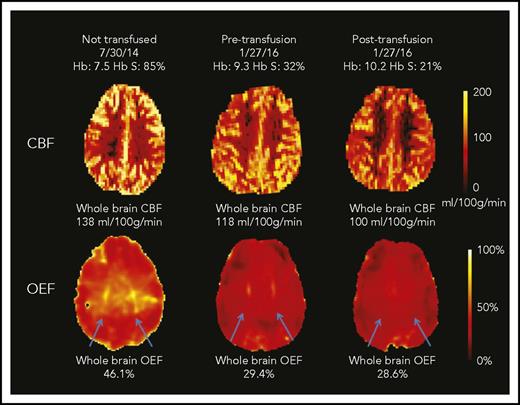

Transfusions decreased whole-brain CBF and OEF, without significant change in CMRO2 (Figure 1). Median CBF decreased from 88.0 (IQR, 73.4-110.8) to 82.4 mL/100 g per minute (IQR, 70.9-99.6; P = .005). Median OEF decreased from 34.4% (IQR, 32.1%-38.5%) to 31.2% (IQR, 29.6%-33.8%; P < .001; Table 2). Examples of CBF and OEF maps are shown in Figure 2. Although collectively both CBF and OEF decreased by an average of 9% posttransfusion, the change in CBF only moderately correlated with change in OEF within individuals (ρ = 0.48; P = .05), suggesting that CBF and OEF changes in response to transfusion effects may vary independently. Tissue-segmented (gray vs white matter) CBF, OEF, and CMRO2 demonstrated a similar response to transfusions as whole-brain values (Table 2).

CBF and OEF maps from a child with SCA. This 7-year-old boy underwent an MRI scan before CTT initiation and again before and after an exchange transfusion (only CTT values included in cohort-level analyses). The whole-brain CBF was highest at his first scan (138 mL/100 g per minute). After 17 months of CTT, his pretransfusion CBF was lower than his initial scan (118 mL/100 g per minute; 14% drop) and further decreased after transfusion to 100 mL/100 g per minute (15% drop). The whole-brain OEF was highest at the first scan (46.1%), with dramatic reduction in OEF measured pretransfusion (29.4%; 38% drop) and only modest reduction posttransfusion (28.6%; 3% drop). His OEF maps were also notable for regionally elevated OEF in the deep white matter (blue arrows), which was most prominent before CTT initiation. This peak OEF was still detectable on the pretransfusion scan, although less prominent. After transfusion, the peak OEF region was absent, with restoration of homogeneous OEF across the brain.

We noted a region of peak OEF within the supraventricular deep white matter in a majority of children with SCA receiving CTT (Figure 2 blue arrows; peak OEF is present pretransfusion and absent posttransfusion). To better define this region and understand the tissue-specific effects of CTT on regional OEF elevation, we averaged all pretransfusion and all posttransfusion OEF maps from the CTT cohort (Figure 4). On the averaged posttransfusion map, this region diminished but remained detectable. To account for hemispheric asymmetries in OEF resulting from vasculopathy or preexisting stroke burden, we evaluated the effect of transfusions on peak OEF within hemispheres, delineated by volume of peak OEF above 36%, 38%, and 40%. We examined 3 thresholds to mitigate a chance association between an arbitrary threshold and transfusion effect. We compared the normalized volume of peak OEF (percentage OEF volume of hemispheric volume) above each threshold before and after transfusion. Peak OEF volumes above each threshold were smaller after transfusion (Figure 4). To evaluate the influence of Hb and Hb S percentage on regionally elevated OEF, we modeled Hb and Hb S percentage as predictors of OEF volumes >40%, finding that Hb was an independent predictor (P < .001), whereas Hb S percentage was not (P = .45). In this model, OEF volume >40% decreased by 3% of total hemispheric volume for every 1-g/dL increase in Hb.